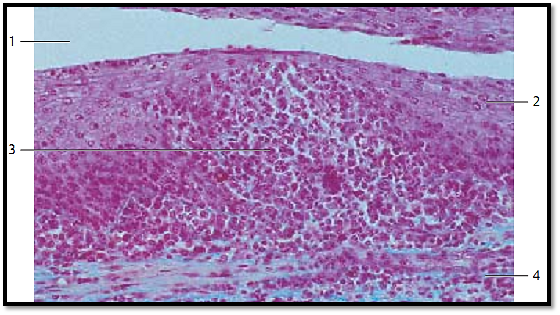

Palatine Tonsil

Longitudinal section of the tonsillar crypt 1 . In the center of the figure, the structure of the multilayered nonkeratinizing squamous epithelium 2 of the oral mucous membranes is completely obliterate d by lymphocytes 3 .It now has the structure of a sponge. The underlying lymphoreticular tissue 4 follows without clear demarcation. The multilayered squamous epithelium to the right and left is for the most part intact. Only a few small, heavier stained lymphocytes reside in this part of the layer. The epithelium of the adjacent crypt wall (top of the figure) appears unchanged. Inflammation (tonsillitis) may cause increased scaling of epithelial cells. This, and the increased presence of leukocytes and microorganisms of the oral cavity, can lead to tonsillar plugs (detritus plugs, tonsillar abscess). Occasionally, these will calcify and form tonsillar stones.

1 Tonsillar crypt

2 Multilayered nonkeratinizing squamous epithelium

3 Lymphocyte immigration and leukocytic diapedesis

4 Lymphoreticular tissue

Stain: azan; magnification: × 200